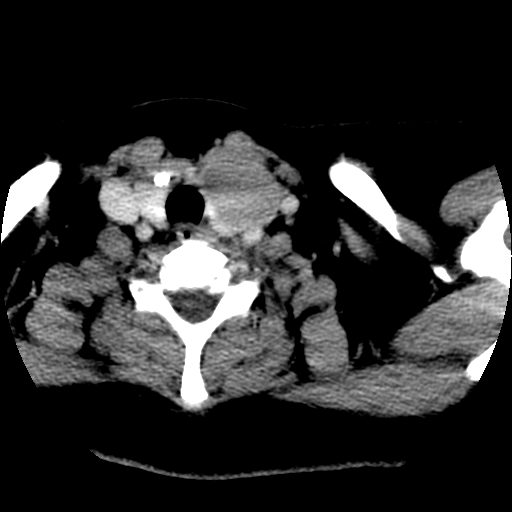

标题: CT25491:女,55岁,发现左侧甲状腺肿块一个月。 [打印本页]

女,55岁,发现左侧甲状腺肿块一个月,彩超示:甲状腺多发结节伴左叶结节液化。

考虑右叶结节性甲状腺肿,伴左叶钙化。主要(1)密度均匀,边境清。(2)病灶与血管界限清。

边界清,无明显强化,考虑考虑甲状腺腺瘤